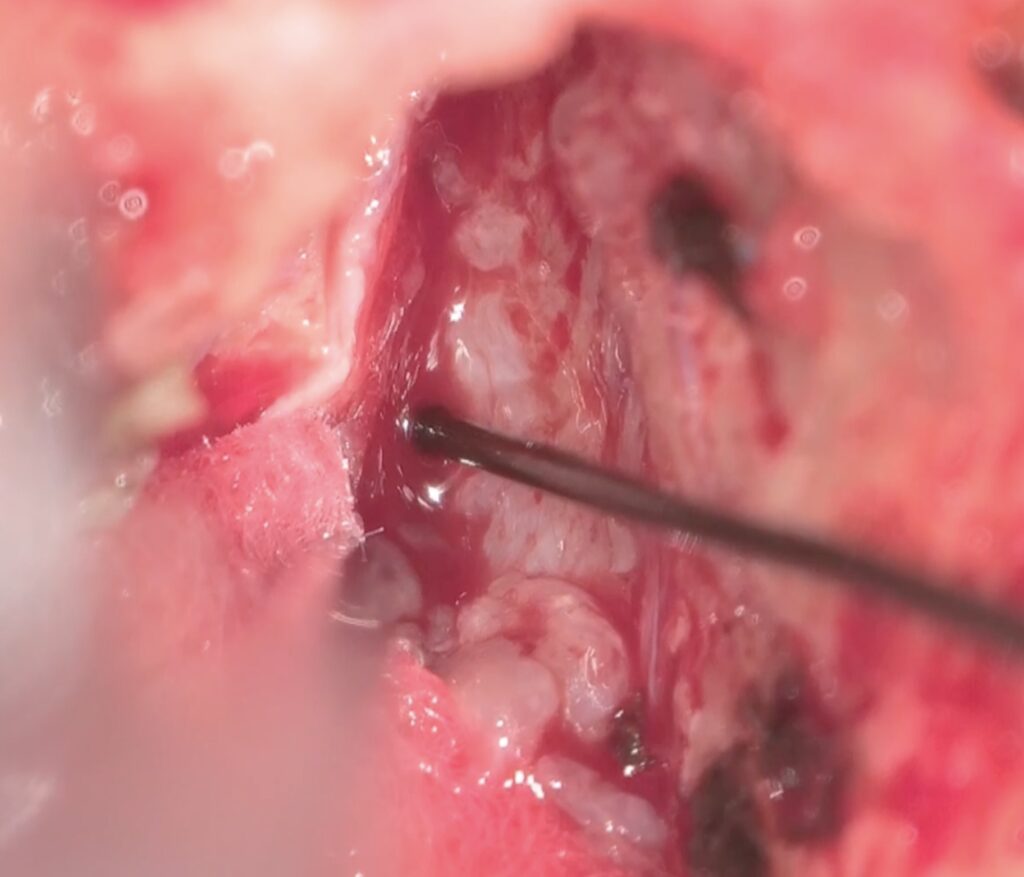

手術は通常通り行われ、顔面神経の麻痺を起こさずに摘出は終了し、うまくいったと考えていました。しかし術後より覚醒障害が続き、強い小脳腫脹を生じたため、術後脳室ドレナージ術、バルビタール麻酔療法、気管切開まで行い急性期を乗り切りました。術前より下肢静脈血栓症を合併していたことと、Petrosal veinが通常より広範囲の静脈環流を行っていたためと考えられます。現在、覚醒し、四肢が動くようになってきました。

手術は通常通り行われ、顔面神経の麻痺を起こさずに摘出は終了し、うまくいったと考えていました。しかし術後より覚醒障害が続き、強い小脳腫脹を生じたため、術後脳室ドレナージ術、バルビタール麻酔療法、気管切開まで行い急性期を乗り切りました。術前より下肢静脈血栓症を合併していたことと、Petrosal veinが通常より広範囲の静脈環流を行っていたためと考えられます。現在、覚醒し、四肢が動くようになってきました。